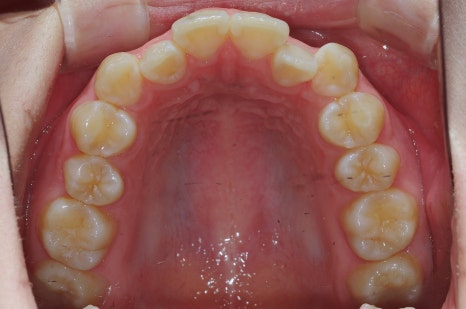

< 스마일디치과 비발치 교정 사례 >

*치료 전후 사진은 환자의 동의하에 게재하였으며, 동일한 환경과 조건에서 촬영된 전후 사진입니다.